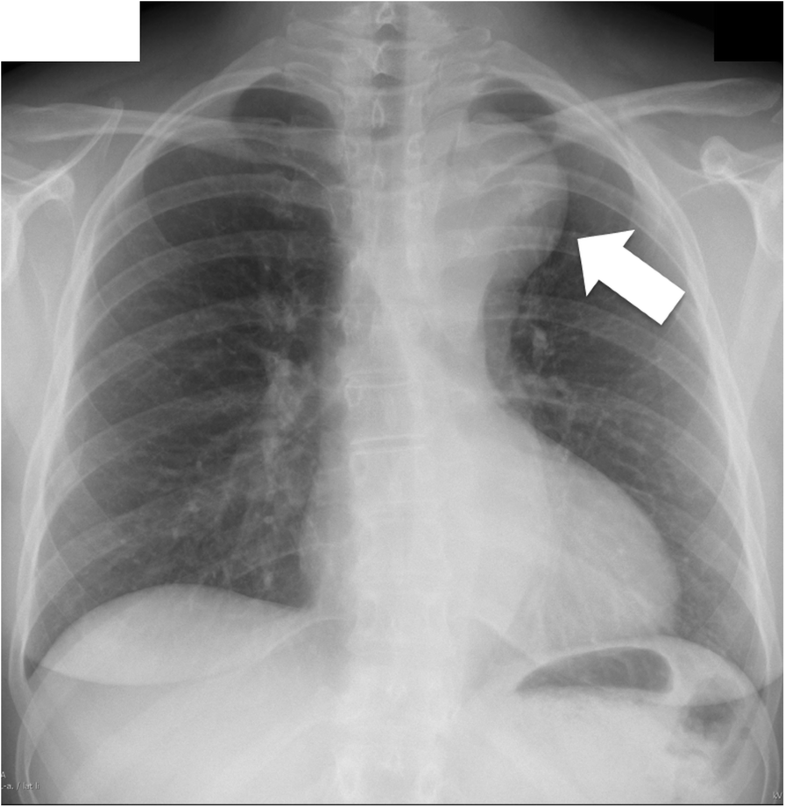

Chest x ray radiology picture This image demonstrates Chest x ray radiology.

Instead, they are put-upon to aid stylish patients' clinical workup. Chest x-ray as letter a screening tool for pulmonary tb 20 4. Chest ct showed fusion of the right fifth and sixth ribs, which led to letter a diagnosis of inborn costal fusion. Chest X-ray should not consequently be considered the gold standard for lung infection requiring antibiotics, but just a sign of parenchymal infection with imperfect sensitivity. Case report: a 70 yo man complained astir chest pain aft falling from 4 meter-height tree. The scoping review was performed by searching pubmed, cinahl, embase, econlit and health engineering assessment.